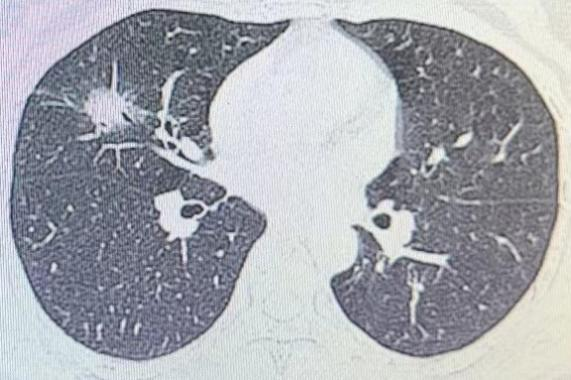

患者因发现左上肺结节住院,经无锡五院心胸外科鱼海峰、呼吸与危重症医学朱峰阅片和讨论,一致认为该患者适合行胸腔镜下LS1+2a+S3切除,创伤小、恢复快,对患者肺功能影响小,可以达到快速康复效果。

一般情况下,影像上依据结节密度将肺结节分为三类。1.纯磨玻璃结节;2.部分实性结节;3.实性结节。其中,实性结节经专业医生排除了良性病变后,其恶性概率最高;其次是部分实性结节,最后是纯磨玻璃密度结节。

3、直径≥5mm的实性结节(排除良性病变),直径>8mm的部分实性结节,直径≥15mm的纯磨玻璃结节,特别是有分叶、毛刺、胸膜牵拉等征象的,应采取积极措施,可以考虑胸腔镜下肺段切除、肺亚段切除或肺楔形切除手术,或在3个月内复查CT,对有长大的,及时采取手术措施。结节缩小,也持续CT监测,随访时间不小于3年。